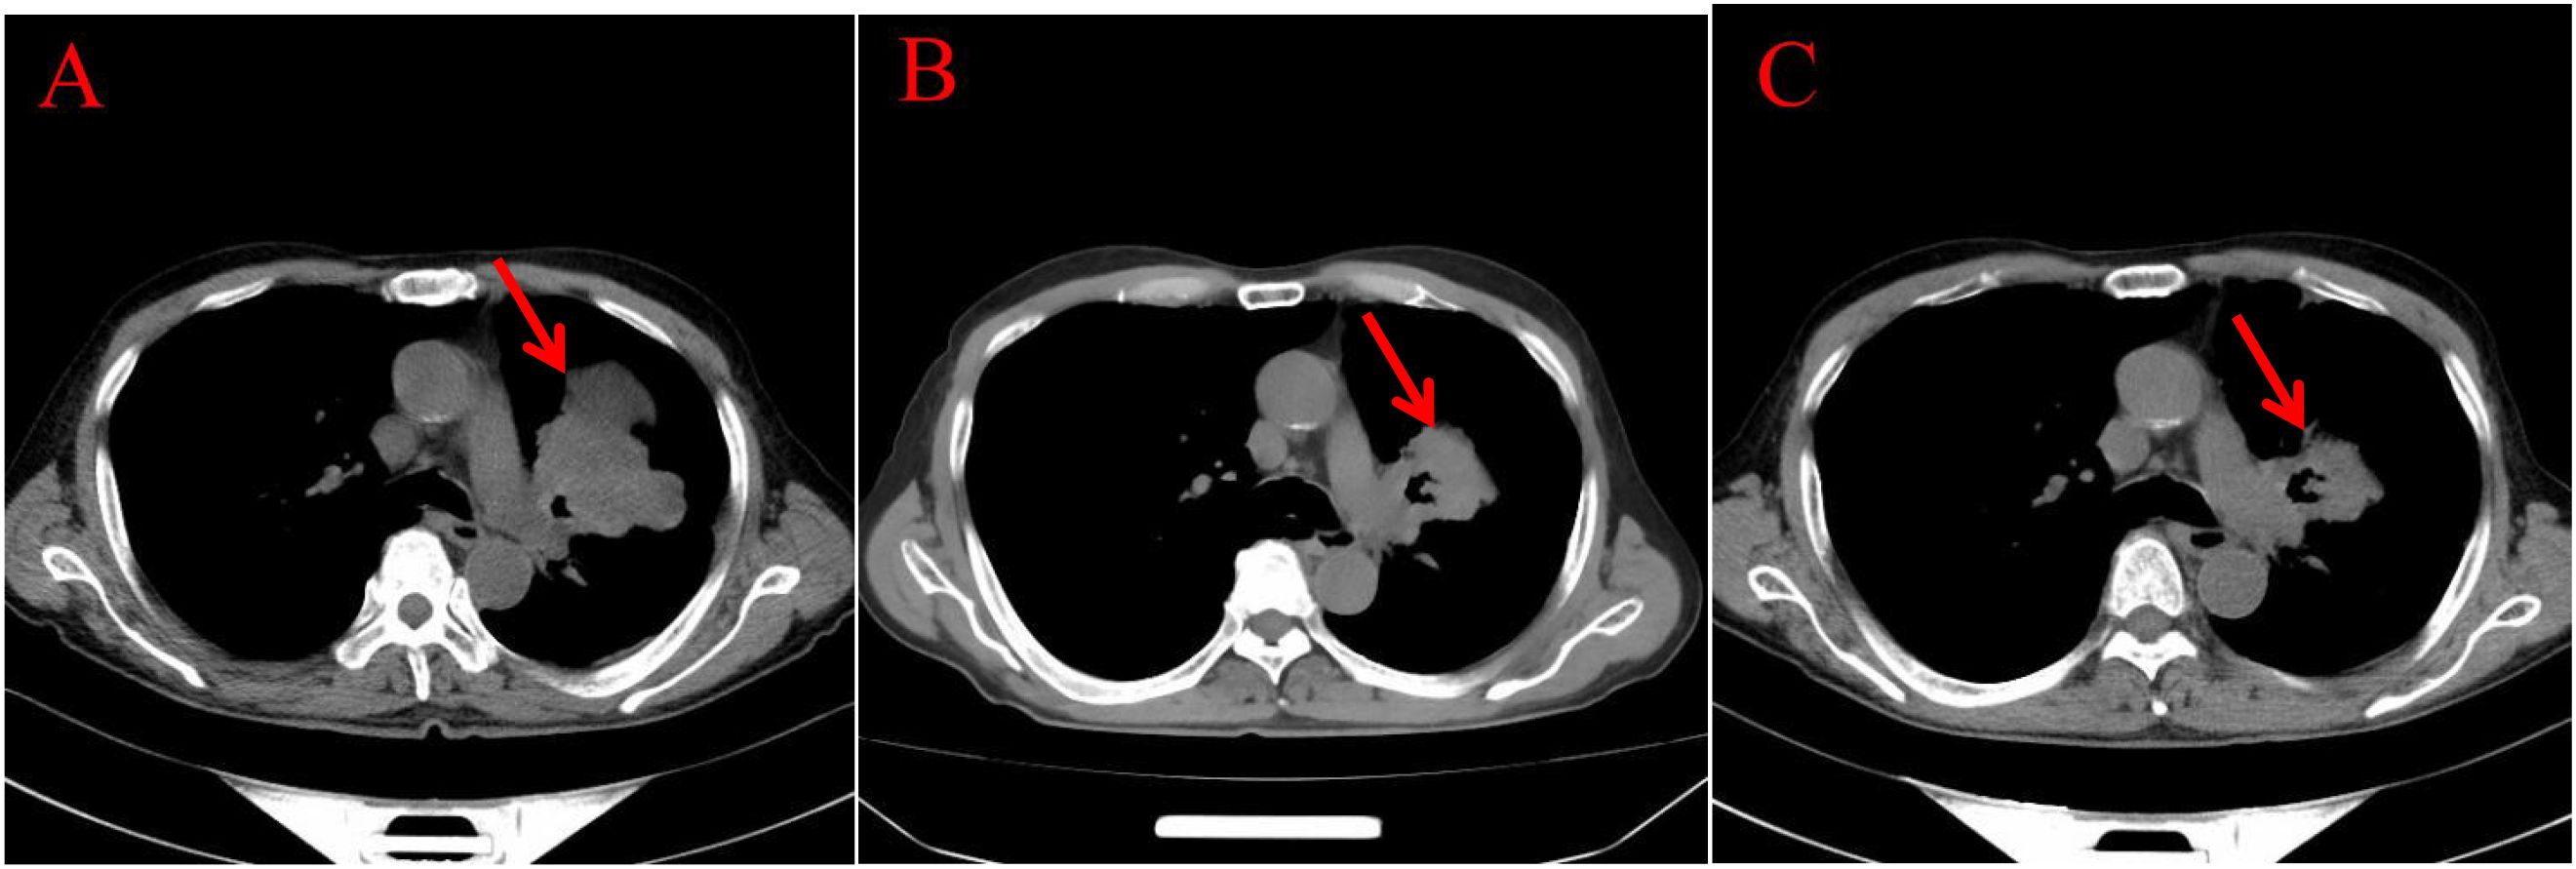

Endoscopic Examination is shown in Figure 2. Pathological Examination is shown in Figure 1. Imaging examinations of the changes in lung, gastric, intestinal and bone lesions are shown in Figures 3–5. The timeline of the diagnosis and treatment process is shown in Figure 6.

Figure 3. Imaging examinations of the changes in lung lesions: (A) (2024.5.2) Central type lung cancer with obstructive pneumonia and atelectasis in the upper lobe of the left lung, similar to the mass in the previous film (January 29, 2024). A huge soft tissue density shadow with a size of approximately 80 * 54mm can be seen near the hilum of the upper lobe of the left lung. (B) (2024.12.11) Central type lung cancer with obstructive pneumonia and atelectasis in the upper lobe of the left lung, with a reduced mass compared to the previous film (May 2, 2024). A huge soft tissue density shadow with a size of approximately 52 * 49mm can be seen near the hilum of the upper lobe of the left lung. (C) (2024.3.25) Central type lung cancer with obstructive pneumonia and atelectasis in the upper lobe of the left lung, with a slightly smaller mass compared to the previous film (December 11, 2024). There is a patchy shadow around the local bronchus in the upper lobe of the left lung, with unclear boundaries.